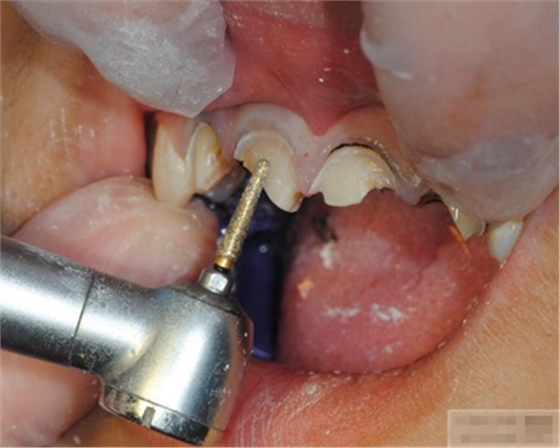

選擇合適的完成鉆制備根管,

通常深入到根管的1/2至2/3處

【纖維樁制作】

修整纖維樁長(zhǎng)度

取出纖維樁,按所需長(zhǎng)度裁截纖維樁 在有水條件下 用切割砂片或車針截取纖維樁,切勿使用鉗子,剪刀或鑷子以免破壞樁的結(jié)構(gòu)

將樹(shù)脂粘接劑均勻涂抹在根管、牙體的粘接面以及纖維樁表面,涂抹兩遍

粘接

將調(diào)好的樹(shù)脂水門汀用口內(nèi)注射頭送入根管

將纖維樁表面涂滿調(diào)好的樹(shù)脂水門汀,安放在根管內(nèi)就位,保持壓力10秒